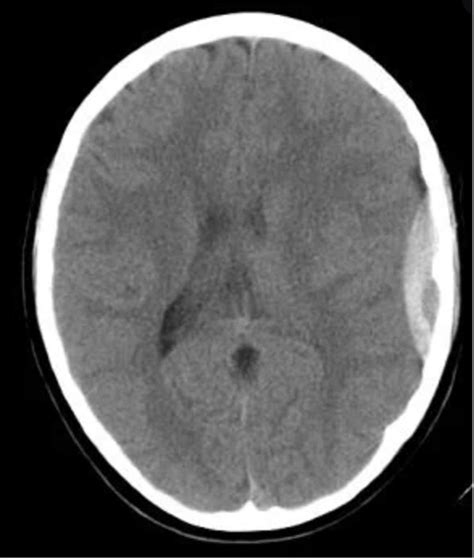

Diagnosis and Imaging

When an uncal herniation brain shift is suspected, time is the absolute priority. Diagnostic imaging is required to confirm the presence and location of the mass effect. A Computed Tomography (CT) scan is the gold standard in an emergency setting because it is fast and widely available. It can reveal:

Finding Clinical Significance

Midline Shift Indicates significant pressure pushing structures across the center of the brain.

Effacement of Basal Cisterns Suggests the brain tissue is being forced into areas where it does not belong.

Temporal Lobe Mass Identifies the primary cause, such as a bleed (hematoma) or tumor.

• uncal herniation on ct scan